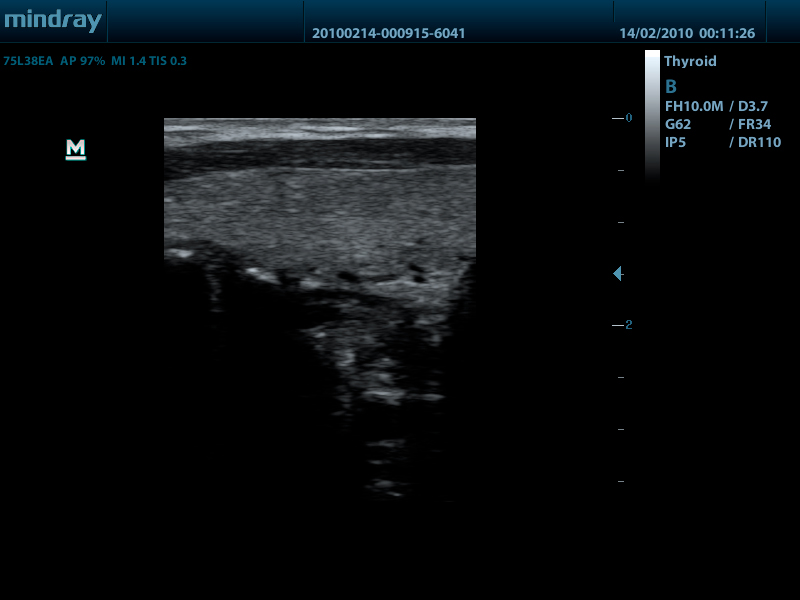

Линейный датчик 75L38EA (5.0/7.5/8.5/10.0/Н8.0/Н10.0 МГц, 38 мм)

Линейный датчик 75L53EA (5.0/7.5/8.5/10.0/Н8.0/Н10.0 МГц, 50 мм)